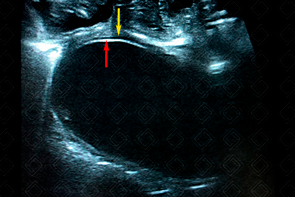

Texto alternativo para a imagem Figura 2. Créditos: Dra. Elazir Mota - Rio de Janeiro/RJ

Descrição da figura 2: Ultrassonografia de abdome da mesma paciente com uso de sonda linear de alta frequência, evidenciando a característica patognomônica de imagem: "parede dupla" ( double wall sign ) (parede mucosa hiperecogênica – seta vermelha – e camada muscular hipoecoica – seta amarela).

• Ultrassonografia de abdome: Por tratar-se de uma doença com pico de incidência na infância, o exame de escolha será a ultrassonografia, por conta de seu baixo custo, acessibilidade e livre de radiação ionizante. Na imagem, o cisto de duplicação apresenta uma característica patognomônica: double wall sign , com sua parede interna hiperecogênica (representando mucosa/ submucosa) e parede externa hipoecoica (muscular) (f iguras 1 e 2);